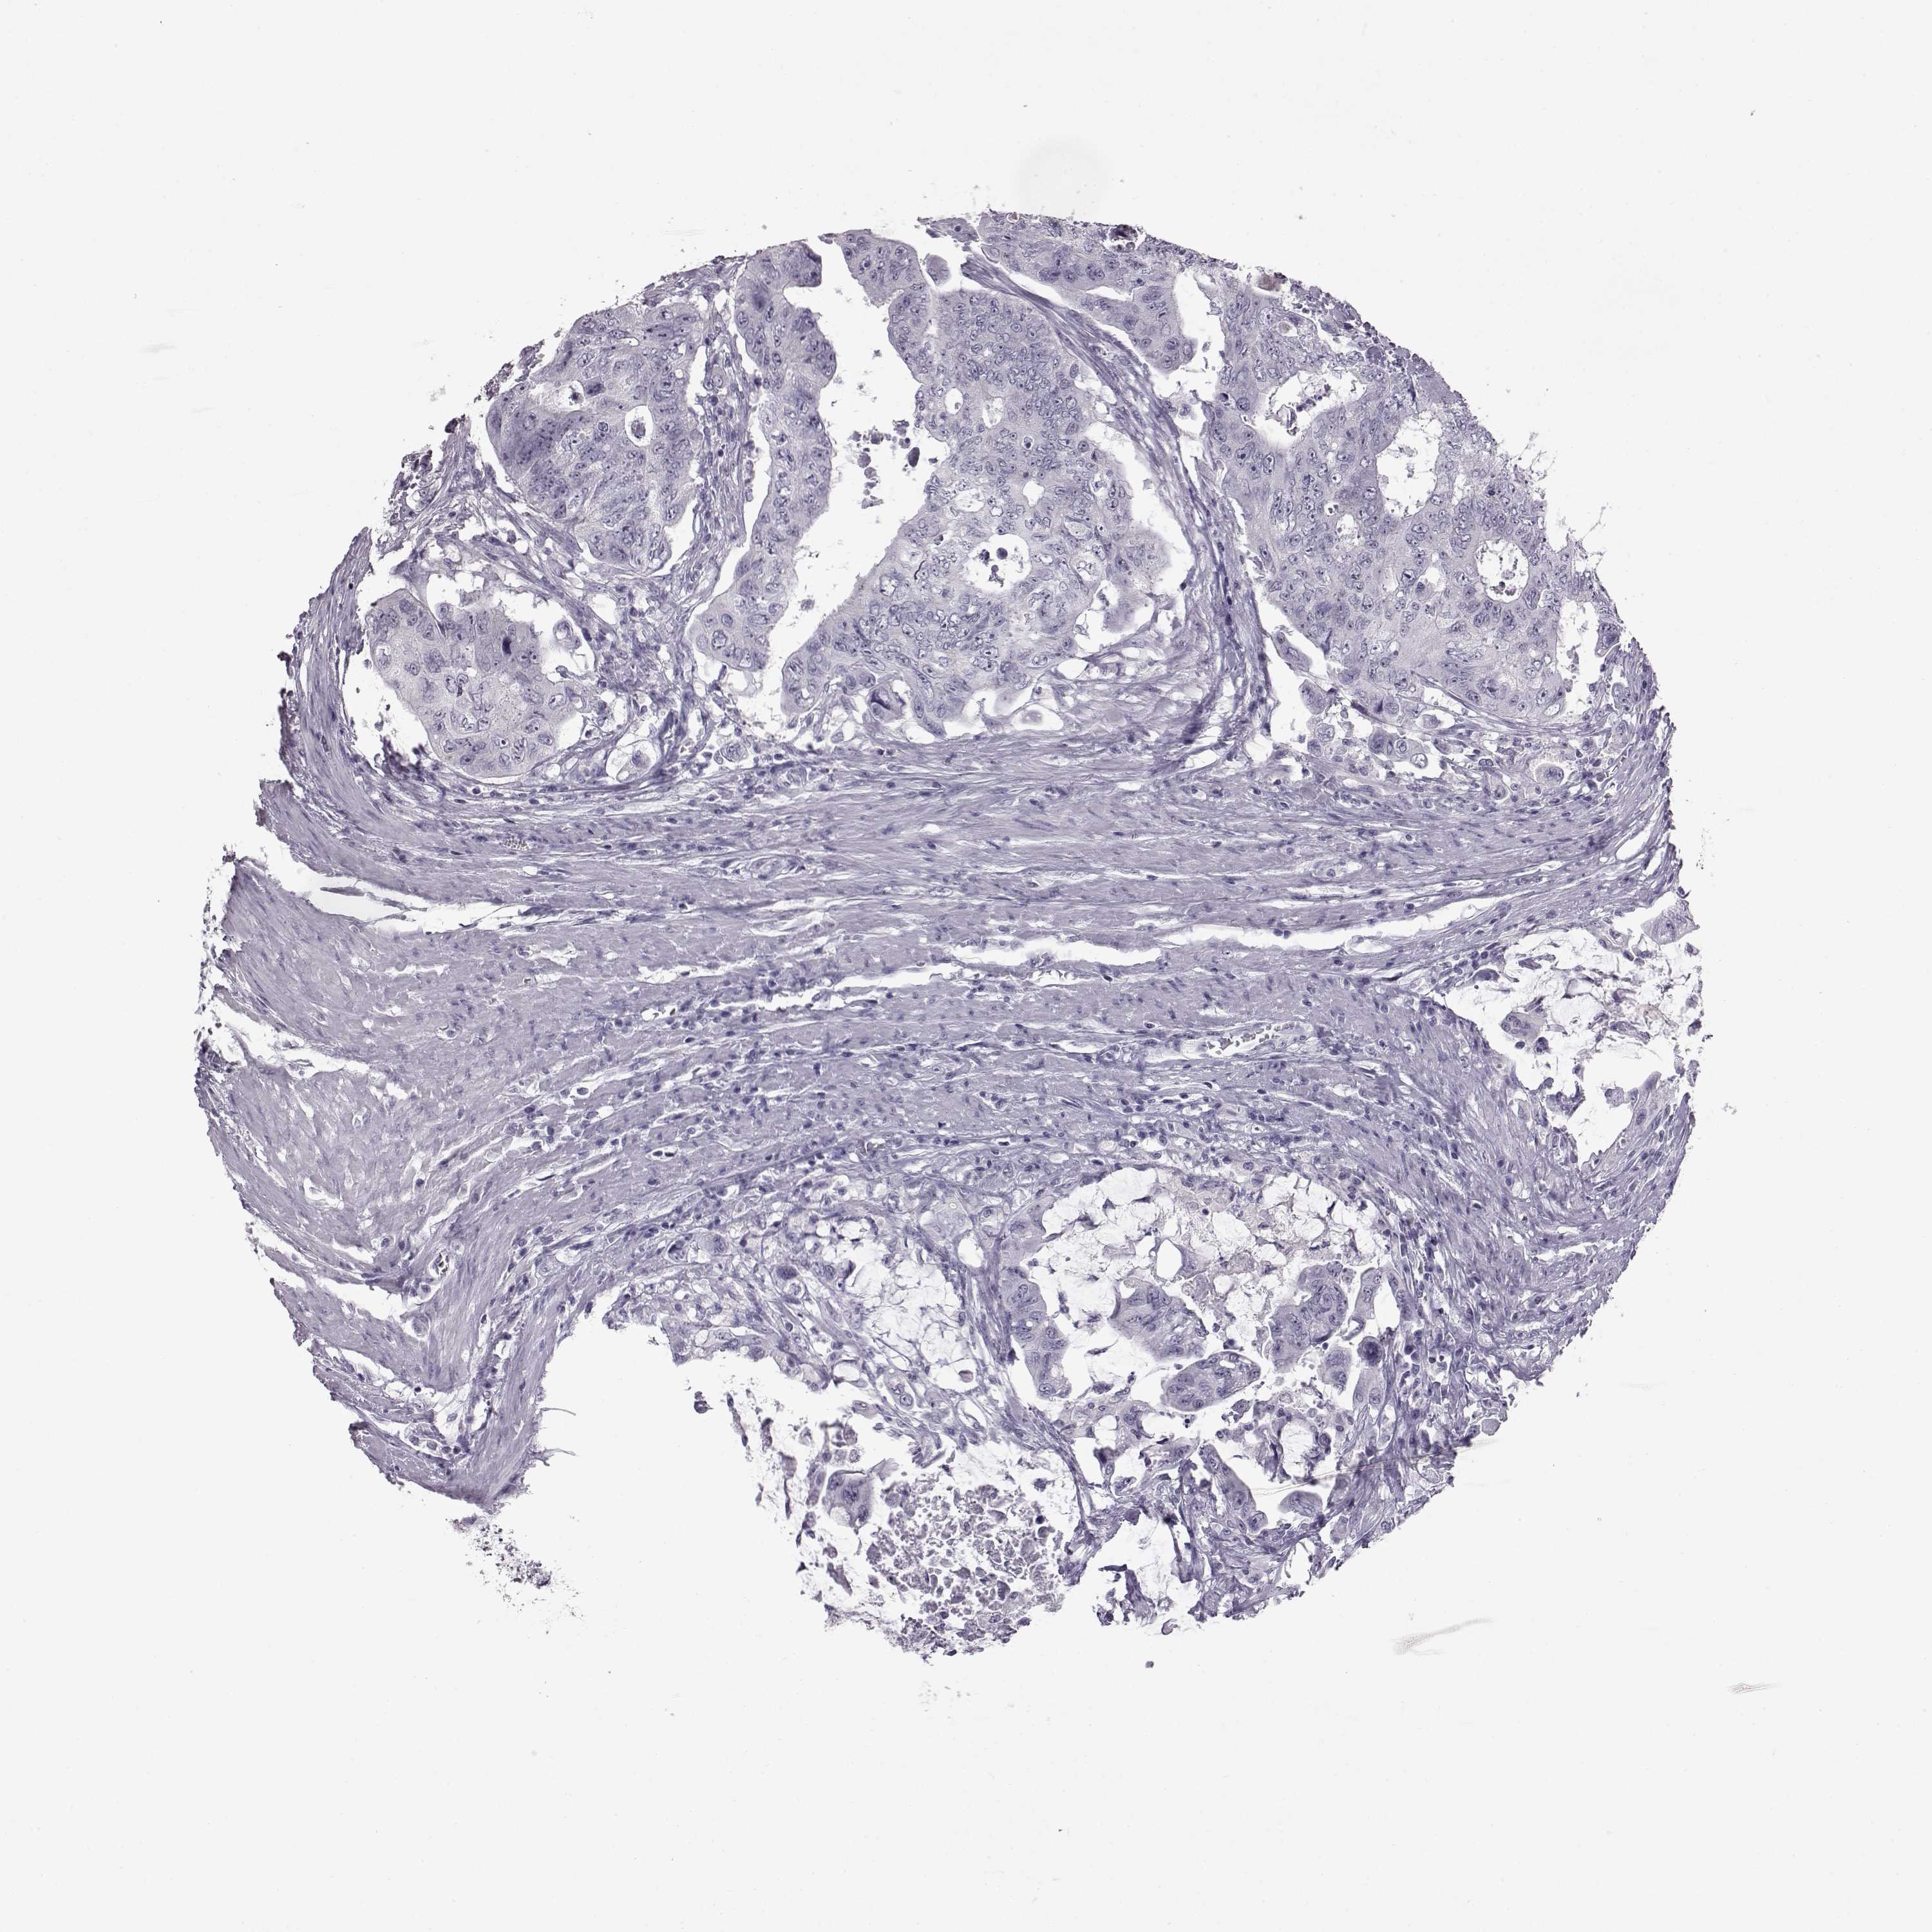

CANCER COLORECTAL CANCER Show tissue menu

Colorectal cancer

Colon adenocarcinoma